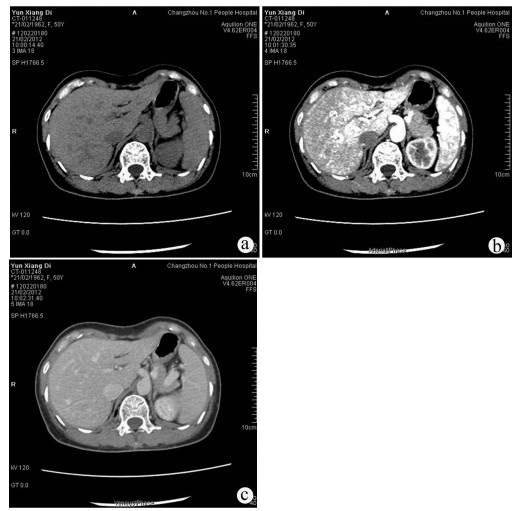

经皮冷冻消融联合无水酒精注射治疗70岁以上老年肝细胞癌患者的效果及安全性分析

罗婧, 吕采红, 杨永平

2022, 38(2): 365-371. DOI: 10.3969/j.issn.1001-5256.2022.02.021

摘要(965) HTML (363) PDF (2738KB)(61)

摘要:

目的  探讨经皮冷冻消融(CRYO)联合无水酒精注射(PEI)对早期老年肝细胞癌患者的疗效和安全性。  方法  回顾性纳入解放军总医院第五医学中心2014年1月—2018年1月收治的92例老年肝细胞癌患者,其中单一CRYO治疗组46例,CRYO联合PEI(联合治疗)组46例。比较两种治疗方式的效果,不良反应及治疗前后肝功能相关指标的变化,并随访患者肿瘤的复发及生存预后情况。正态分布的计量资料两组间比较用t检验;非正态分布的计量资料两组间比较采用Mann-Whitney U秩和检验。计数资料两组间比较采用χ2检验。两组的生存时间采用Kaplan-Meier方法进行生存分析,并用log-rank检验生存曲线的差异;通过Cox回归法确定影响生存预后的独立危险因素。  结果  联合治疗组和CRYO组初次消融的有效率分别为89.1%和73.9%,组间差异无统计学意义(P>0.05)。CRYO组和联合治疗组患者术后总生存率和无瘤生存率间的差异均无统计学意义(P值均>0.05),但联合治疗组患者术后第1、2和3年局部肿瘤进展率分别为20%、21%和21%,明显低于CRYO组的30%、46%、46%(χ2=4.187,P<0.05)。多因素Cox回归分析提示行单一CRYO治疗可能是局部肿瘤进展率的独立危险因素(HR=2.206,95%CI: 1.003~4.850, P=0.049)。在不良反应的发生率上两组间差异没有统计学意义(P>0.05),但CRYO组有3例严重不良反应,联合治疗组未出现严重不良反应。  结论  对于早期老年肝细胞癌患者,CRYO联合PEI治疗较单纯CRYO治疗安全有效,能明显降低局部肿瘤进展率。